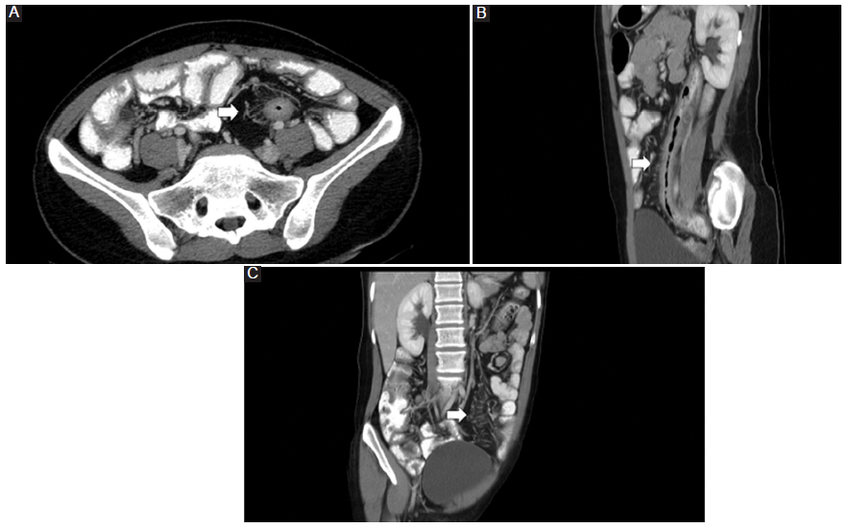

La TC permite identificar la hipervascularización del mesenterio, la elevación de la atenuación de la grasa mesentérica (20-60 UH) y el aumento en el espacio entre la vasa recta, que dan la apariencia de los dientes de un peine (Fig. 1) (3,4. La resonancia magnética (RM) también permite identificar los hallazgos que configuran el signo (Fig. 2) (3,5.